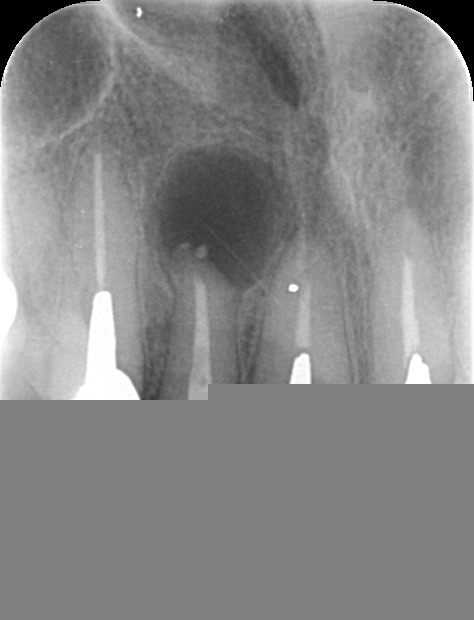

上顎側切歯再根管治療(抜歯回避症例)

性別:30代女性

部位:上顎側切歯

主訴:上顎側切歯の抜歯の可能性及び再根管治療の可否診断について他院よりご紹介.

3DCT及びデンタルX線撮影、及び歯周組織検査を行い保存可能と診断

仮歯を作製装着し、3ヶ月後の検診において治癒傾向が確認でき次第

主治医の元で上部作製を依頼予定